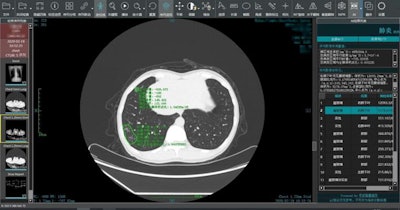

Ping An's algorithm can analyze medical images for signs of infection with COVID-19. Image courtesy of Ping An Insurance.

Clinical data were used to train AI model to detect signs of COVID-19 infection in patients. It can conduct a comparative analysis of multiple CT scans of the same patient and measure changes in lesions. It assists doctors in diagnosing, determining the severity of the patients' conditions, and evaluating patients for COVID-19 swiftly and effectively, according to the company.